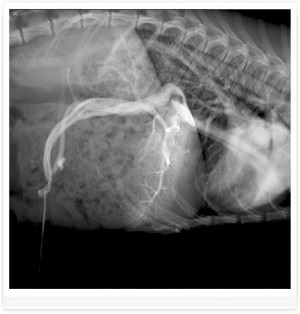

Foto 1. șunt ductul venos - o navă care leagă vena ombilicala la vena cava caudală a fătului

Foto 3. shunts portocaval - venei porte drenaj în vena cava caudală

Foto 4. shunts portocaval - venei porte drenaj în vena cava caudală

Diagnosticul EXEMPLU și tratamentul shunt. Câine rasa Yorkshire Terrier